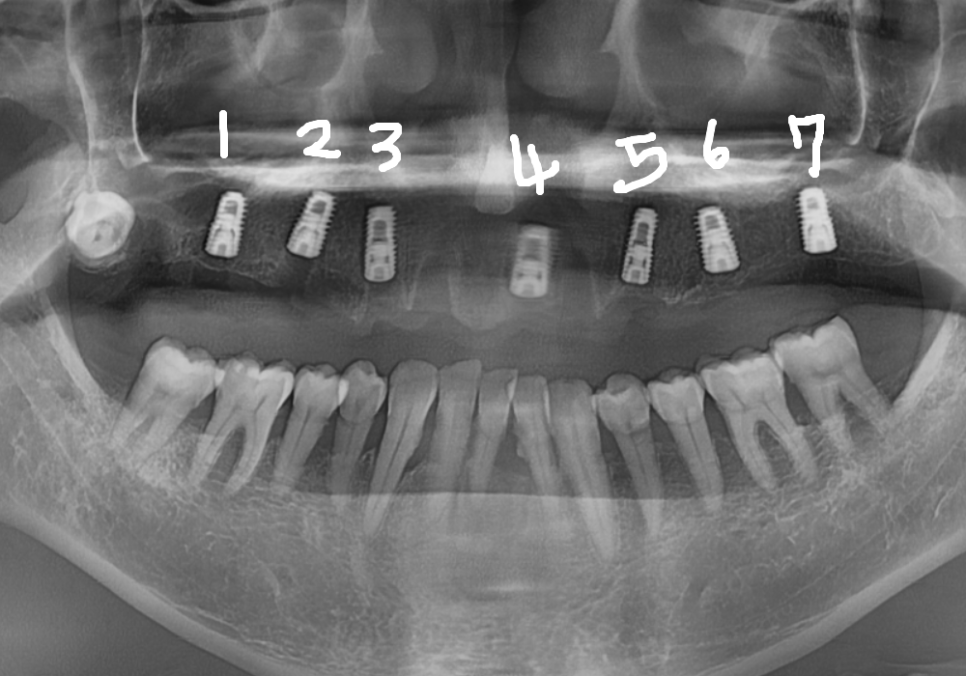

수술은 아주 잘 끝났지만,

그날 바로 치아머리를 올리지는 않습니다.

여기엔 아주 중요한 이유가 있는데요.

임플란트는 우리 뼈와 완벽하게

'한 몸'이 되어야 하는데,

뼈세포들이 임플란트 표면으로 단단히

달라붙을 시간이 꼭 필요하거든요.

그래서 위턱의 경우,

특히 상악동 거상술까지 했기에

약 5개월 정도 충분히 뼈와 굳기를 기다립니다.

그동안은 식사가 가능하도록

임시 틀니를 제작해 드렸어요.

5개월 뒤, 임플란트가 뼈와 단단히

하나가 된 것을 확인하고 본을 뜰 준비를 합니다.